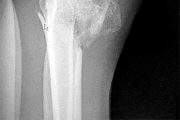

Question 44:

A 62-year-old male of East Asian descent presents with progressive myelopathy. His imaging is shown. Which of the following specific CT findings is the strongest independent predictor of a dural tear during an anterior cervical corpectomy and decompression for this condition?

Correct Answer: The 'double-layer' sign

Explanation:

The image indicates Ossification of the Posterior Longitudinal Ligament (OPLL). The 'double-layer' sign on a CT scan is highly specific for dural ossification and represents a significant risk for dural tears during anterior decompressive surgeries. It consists of anterior and posterior hyperdense ossified rims separated by a central hypodense non-ossified ligament.